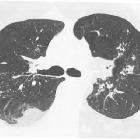

Radiographic features

CT

- round or oval in shape

- almost always seen adjacent to a pleural surface

- there is associated adjacent pleural abnormality, e.g. pleural thickening or pleural effusion

- comet tail sign : produced by the pulling of bronchovascular bundles giving the shape of a comet tail

- crow feet sign

- as it represents collapsed lung, it commonly demonstrates a typical parenchymal enhancement

- posterior lower lobes are most commonly involved and, sometimes, bilateral or symmetrical